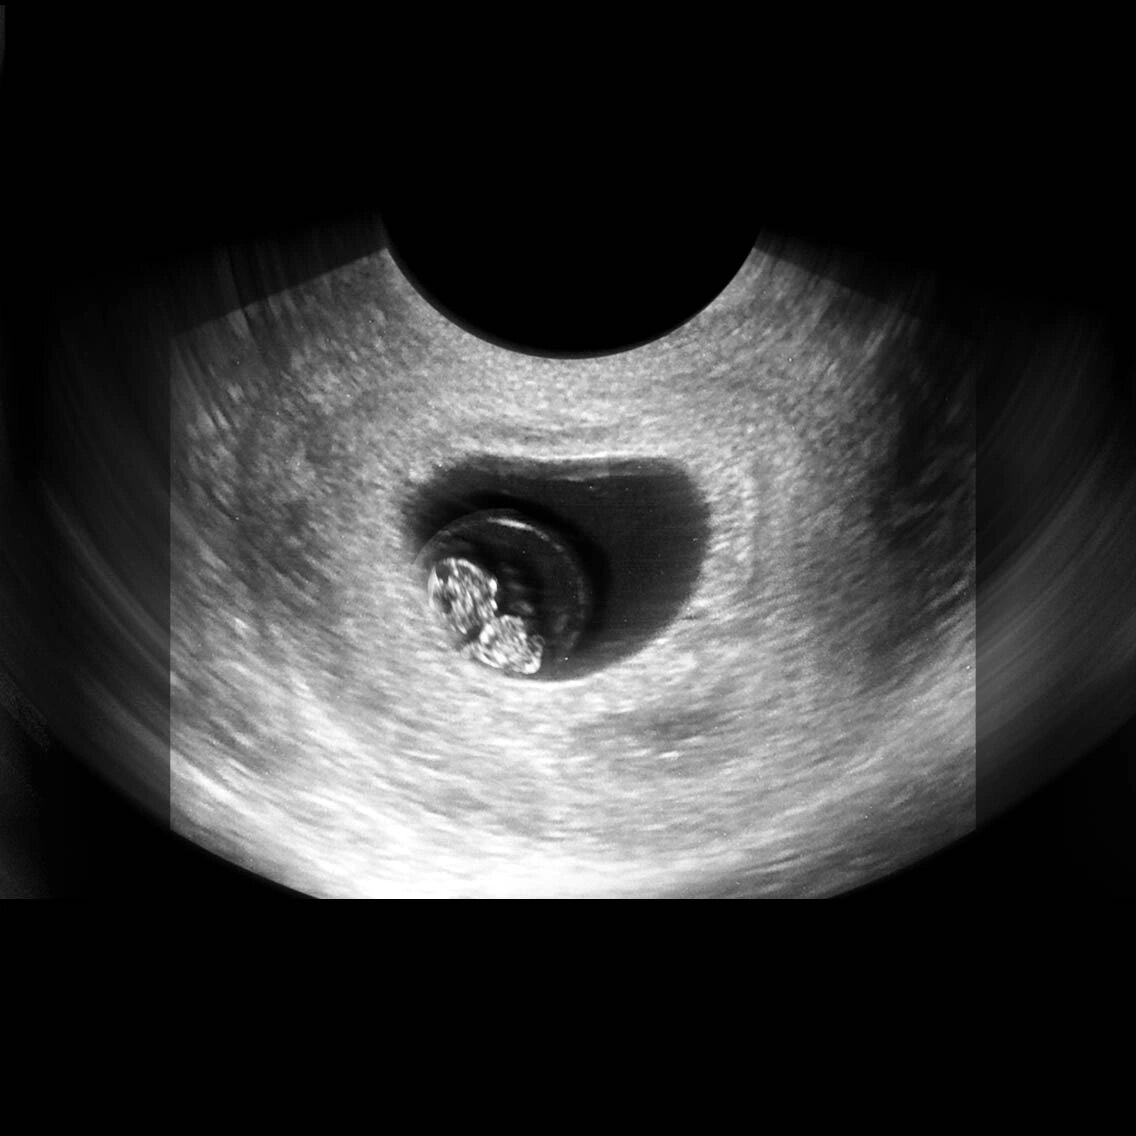

孕七周,有胎心胎芽啦!

图片尺寸1008x1344